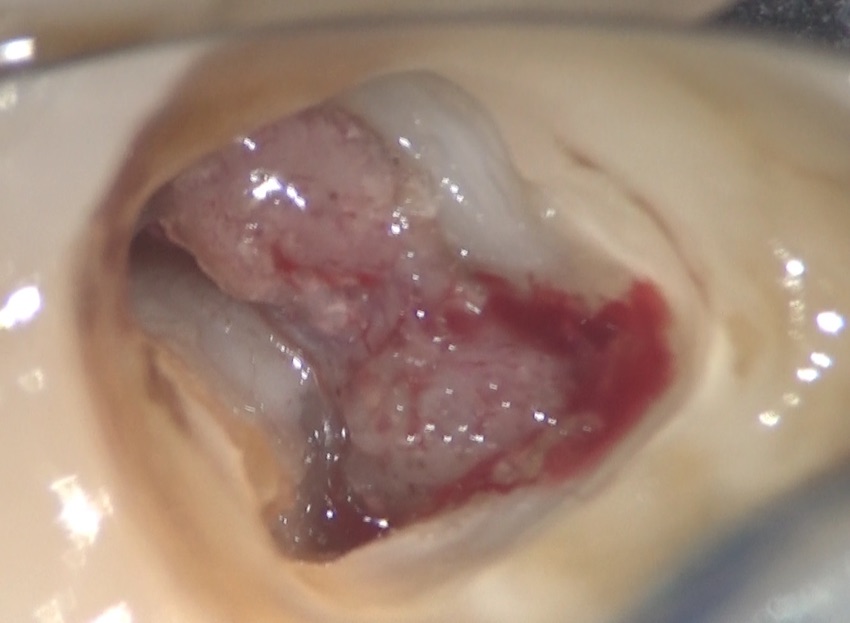

これが、歯髄と呼ばれる軟組織、いわゆる神経、と呼ばれているものです。

この神経を洗い流し、この軟組織の入っている部分のその上の部分取り除いた部分です。左右に見えるのが、神経の管、つまり根管の入り口です。